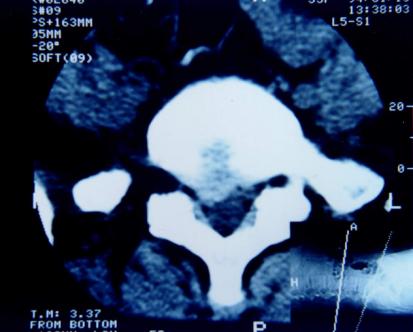

CT检查:具有确诊价值。将人体的脊柱的通过CT扫描仪,各个平面扫下来,总能看到你想要看到的层面,但CT只能看到密度较高的东西,如骨头、骨质,而对于神经等相对“软”的东西,敏感性不佳。

磁共振检查:跟CT一样,具有确诊价值,同时由于其成像原理,对于观察神经以及是否存在神经压迫水肿信号,有独特的优势,也是目前诊断腰椎间盘突出,明确神经压迫的主要检查,老百姓没学过医的也可以看得到的“突出”!

症状是典型的腰腿痛症状,还伴有麻木(灯泡一闪一闪了)神经异常放电,当时还没有学医的我去了家里的镇医院做了一个磁共振检查,当时拿到黑胶片的时候,连一个刚成年的我都看到了我那明显突出的“椎间盘”,白白的亮闪闪的......